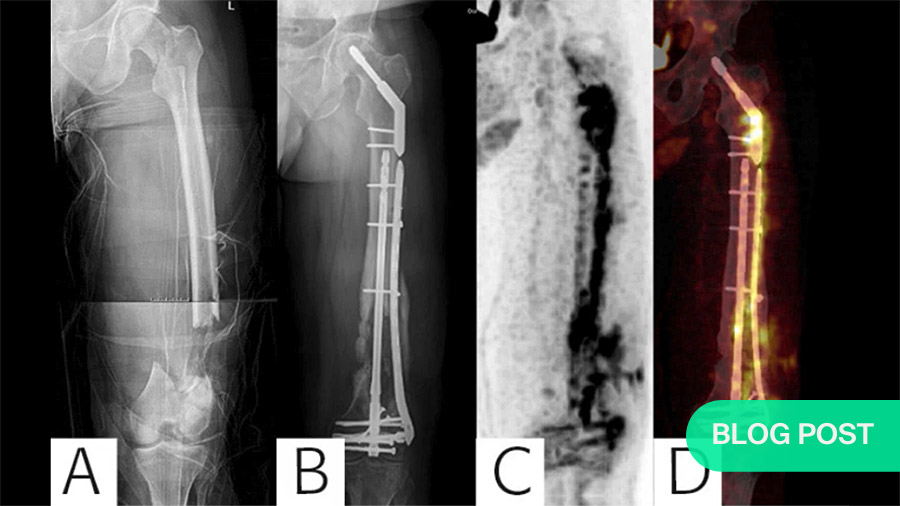

F-FDG-PET scans or white blood cell (WBC) scintigraphy?

In addition, as non-union is suggestive of an FRI, radiological images should be examined very closely. If available, F-FDG-PET scans show high diagnostic accuracy for FRIs 2, but are only recommended 1-6 months after the initial reduction. For earlier testing, white blood cell scintigraphy 3 shows excellent diagnostic value. However, whereas F-FDG-PET imaging only requires a single scanning session, WBC scintigraphy requires two.

The figure at top of page was published in the following paper:

Diagnosing Fracture-Related Infection: Current Concepts and Recommendations.

Govaert GAM, Kuehl R, Atkins BL, Trampuz A, Morgenstern M, Obremskey WT, Verhofstad MHJ, McNally MA, Metsemakers WJ; Fracture-Related Infection (FRI) Consensus Group. J Orthop Trauma. 2020 Jan;34(1):8-17. doi: 10.1097/BOT.0000000000001614.